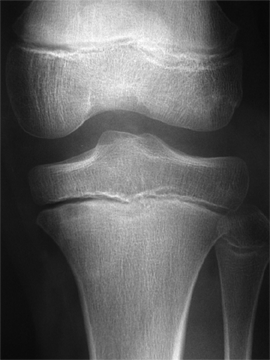

Pathologies infectieuses osseuses

Il s'agit des ostéomyélites sub-aigues et chroniques.

Ce sont des infections

bactériennes des os qui se développent doucement, sans

provoquer des signes généraux (ni fièvre, ni frisson,

ni altération de l'état général) et qui

s'accompagnent de douleurs.